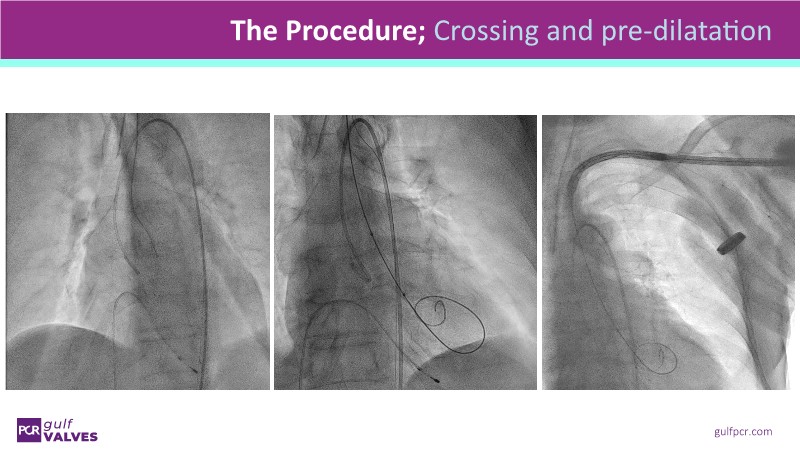

Discover a selection of cases showcasing the key features of the Navitor Valve System and its clinical applications. This session explores auxiliary access, the use of Navitor in alternative access and complex PCI, its performance in challenging peripheral anatomies, and innovative outcomes with the Vantage 30D system.